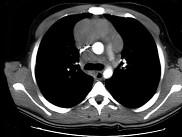

问题 21岁,男,1个月前触及颈部淋巴结肿大,现有上腔静脉综合征,请结合胸片和CT,选出最可能的诊断 ( )

选项 A.结节病 B.淋巴结核 C.转移性淋巴结肿大 D.淋巴瘤 E.胸腺瘤

答案 D